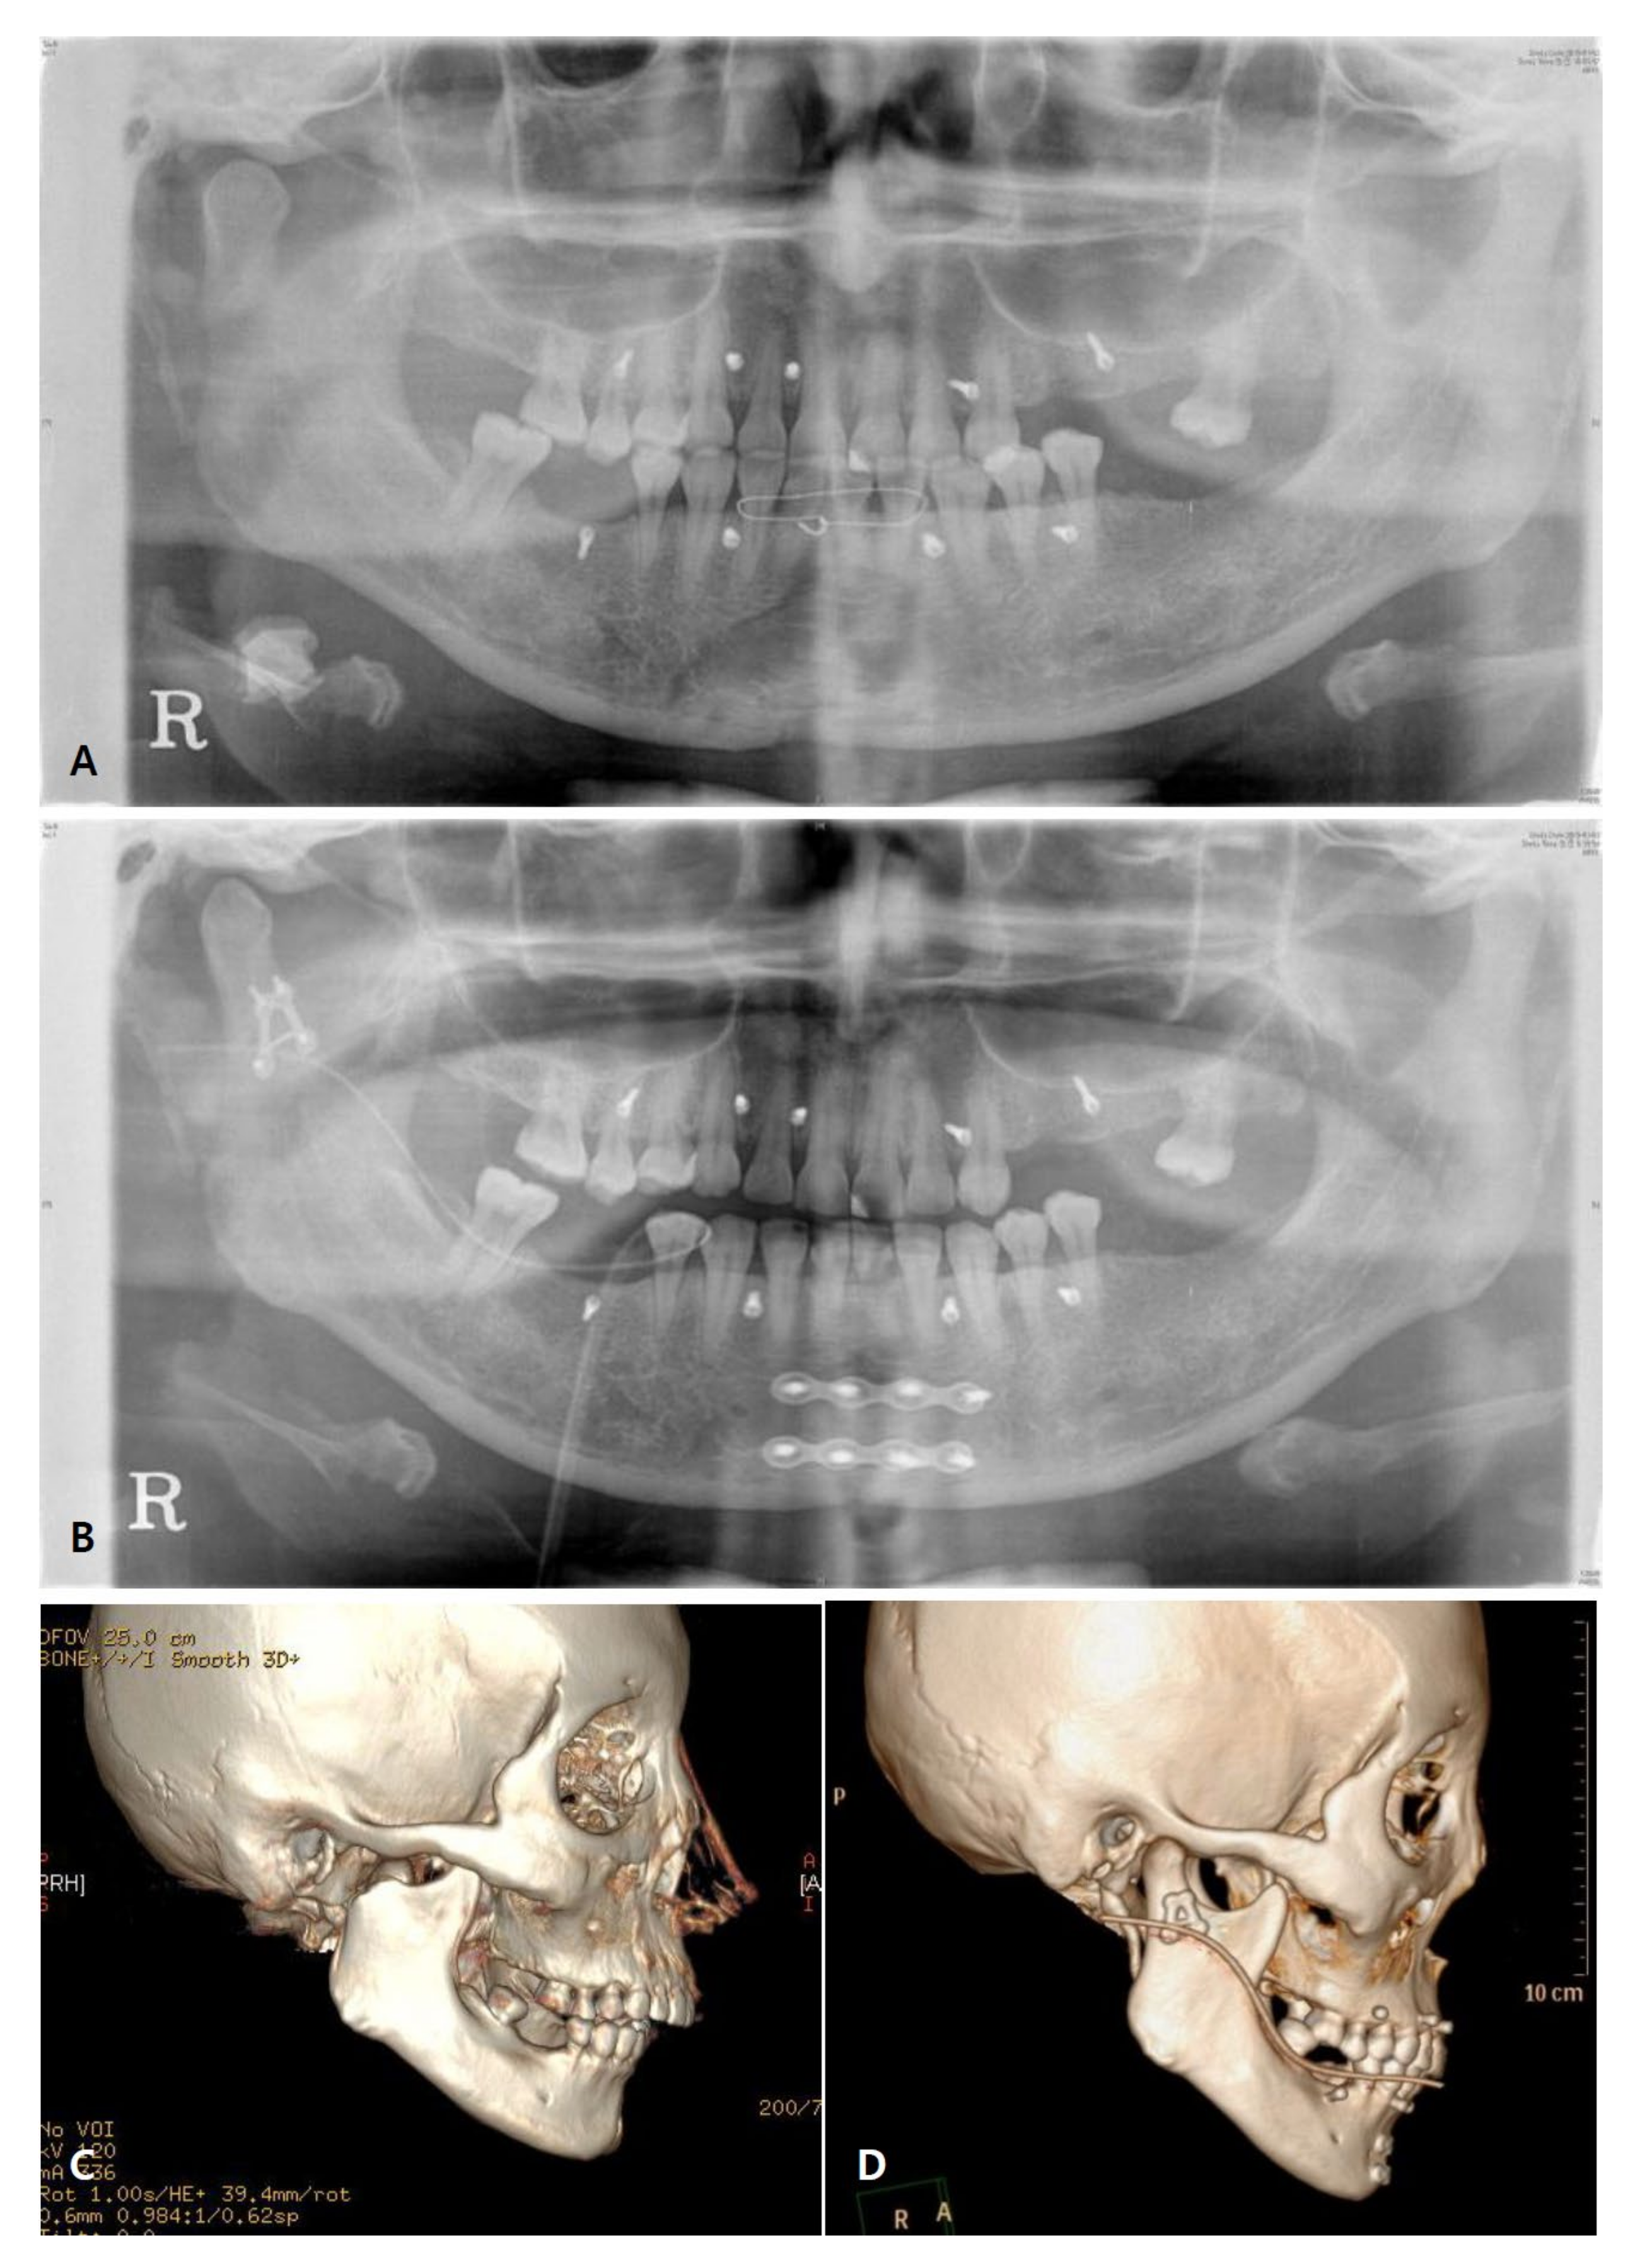

3.3. Radiographic Evaluation

| Variables | Non-Operated Side (n = 18) | Operated Side (n = 18) | p-Value * | |

|---|---|---|---|---|

| Length (mm) | Mean ± SD | 65.68 ± 6.77 | 65.02 ± 6.48 | 0.205 |

| Median (min–max) | 65.33 (52.10–79.40) | 66.77 (48.16–74.13) | ||

| Angle (n°) | Mean ± SD | 166.31 ± 7.10 | 164.95 ± 8.26 | 0.099 |

| Median (min–max) | 168.10 (143.00–175.20) | 165.30 (142.50–179.50) | ||